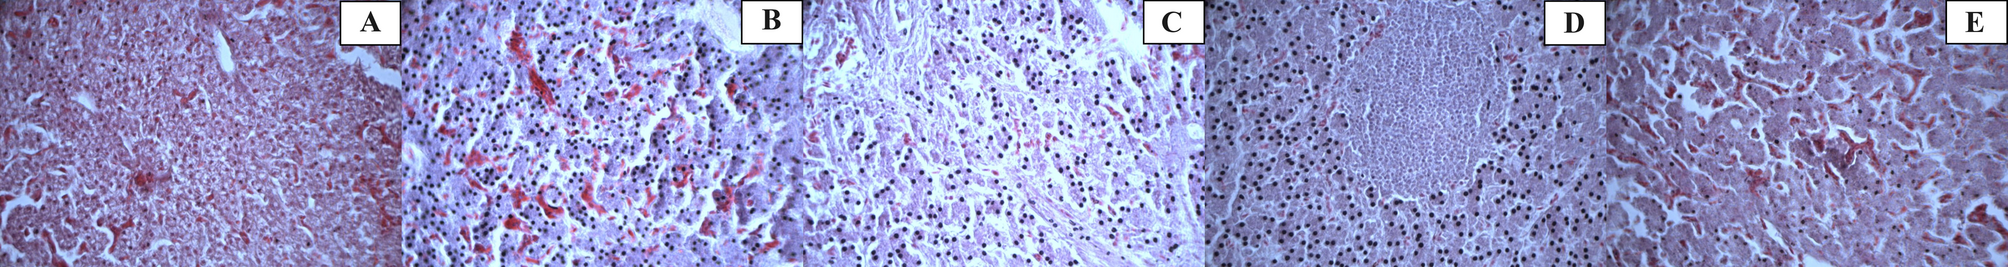

Fig. 1

Light micrographs of broiler chicken liver tissues (hematoxylin and eosin stain, H&E). (a) presence of vacuoles (40×); (b) presence of congestions (40×); (c) presence of fibrosis (40×); (d) presence of necrosis (40 ×); (e) presence of parenchymal eclipse (40×).